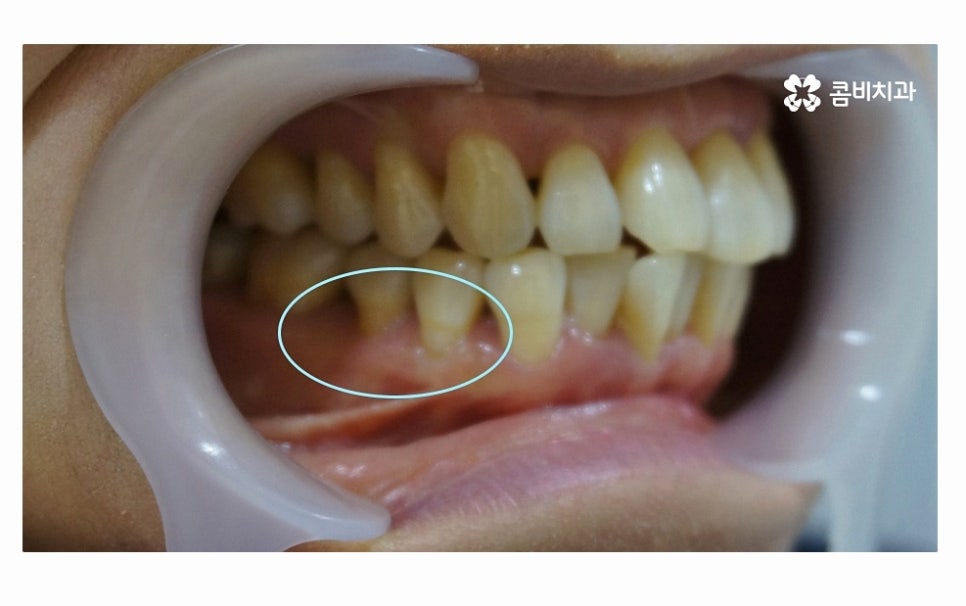

사진에서 보시는 것처럼 치아 사이에 빈 공간도 많고

잇몸이 내려앉아서 치아의 하단부도 많이 드러난 상태인데

치아를 잇몸이 제대로 감싸주지 못하고 이렇게

내려앉게 될 경우 치아도 많이 시리게 되고

이처럼 잇몸질환이 심해지면 치아의 상실로 이어질 수 있고

잇몸이 퇴축되어 심미적으로도 좋지 않지만

치아를 단단하게 고정해야 하는 잇몸 뼈가 치주염으로 인해

파괴되면 치아를 잃게 될 수 있는데 더 큰 문제는

잇몸에 발생한 염증이 주변 잇몸이나 턱뼈까지 손상을